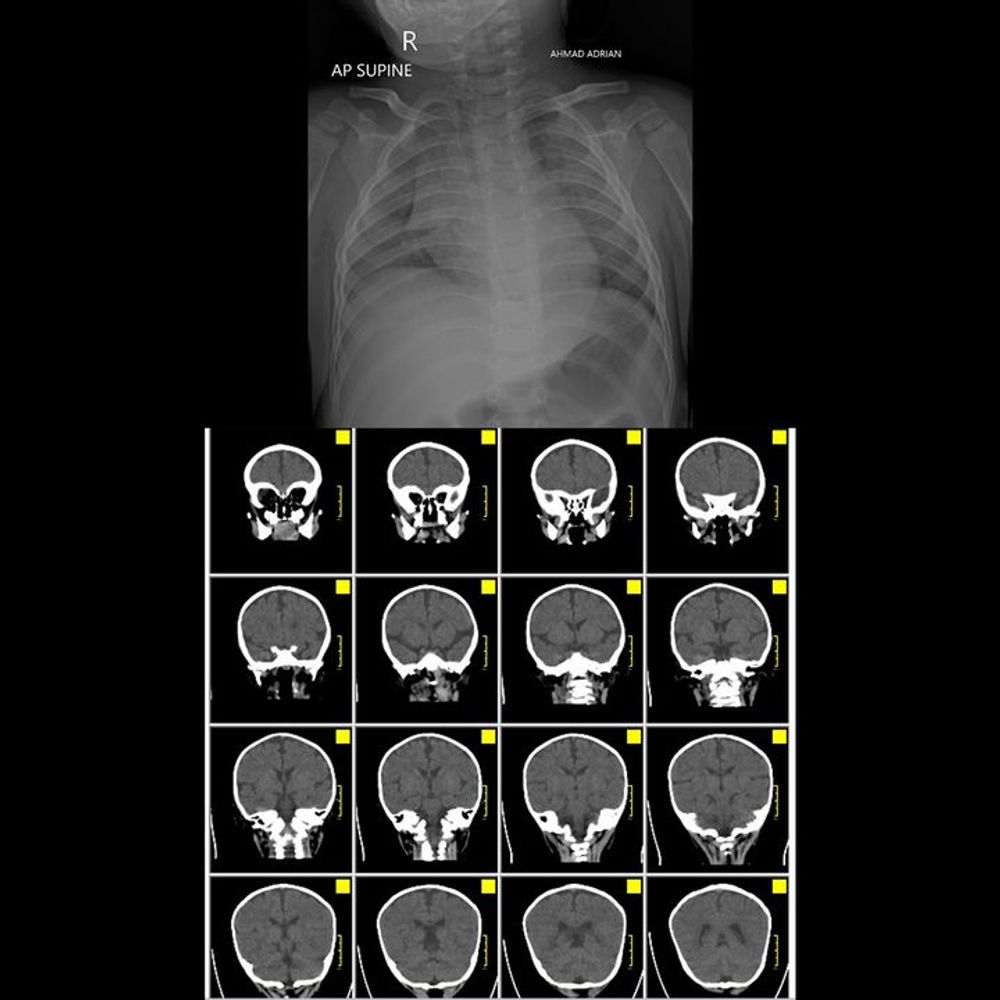

Baby Andrian was born healthy, bringing joy and hope to his parents. But their happiness quickly turned into a nightmare when Andrian suddenly developed a high fever followed by severe seizures. Since then, his tiny body has been fighting for life against five critical complications at once—including brain inflammation, lung infection, repeated seizures up to 15 times a day, and severe nerve damage.

His condition forces him to rely on medical machines, feeding tubes, and strong medications just to stay alive. Despite continuous treatment, Andrian often falls into critical condition, with seizures that sometimes last nearly an hour. Doctors revealed that dangerous bacteria have spread to his vital organs, leaving his life hanging by a thread.